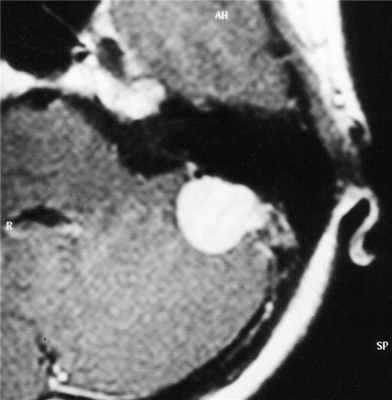

Менингиома вторая по частоте опухоль мосто-мозжечкового угла после невриномы VIII пары. Как и при других локализациях менингиома чаще встречается у женщин среднего возраста. Мелкую, расположенную внутри канальца менингиому, при МРТ невозможно отличить от невриномы. Однако, внутриканальцевый компонент больше характерен для неврином. Крупная менингиома при МРТ головного мозга имеет типичное для этих опухолей плоское основание и соответственно форму полукруга, часто распространяется в среднюю черепную ямку. Интенсивность сигнала от менингиомы на Т2-взвешенныъ МРТ обычно ниже, чем от невриномы. Структура опухоли при МРТ может быть как однородной, так и гетерогенной. В пользу менингиомы говорит прорастание верхушки пирамиды, разрушение ее структуры с элементами склероза. Невринома и нейрофиброма продавливают и ампутируют верхушку пирамиды. В дифференциальной диагностике помогают и другие МРТ признаки, типичные для менингиом: симптом “хвоста”, ликворное кольцо и смещение сосудов. Контрастирование МРТ усиливает сигнал от менингиомы также хорошо, как и от невриномы.

МРТ головного мозга. Менингиома мостомозжечкового угла (стрелки). Аксиальные Т2-зависимая МРТ и Т1-зависимая МРТ с контрастированием.